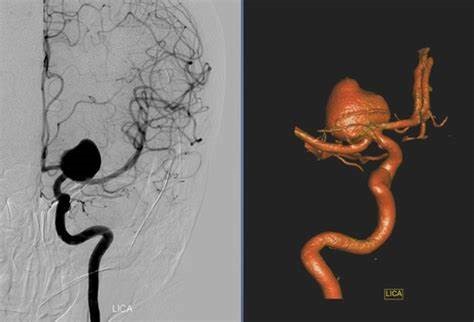

要想知道脑内是否有动脉瘤,早期筛查很重要。目前筛查的方法主要有两种,一种为计算机辅助断层扫描血管造影(CTA),可清晰显示脑血管的情况;另一种为磁共振血管造影(MRA),也可将血管显像以发现脑动脉瘤。这两种方法均能合适检查出大多数超过3-5毫米的脑动脉瘤。建议40-50岁人群,每年体检时可以进行脑动脉瘤筛查。另外,如果家庭成员中有人患脑动脉瘤,其他人较好也在医生指导下做脑血管造影等检查。

目前,脑动脉瘤的治疗已经成熟了,目前常用的两种方法,一种是开颅夹闭动脉瘤;另一种是微创的介入栓塞动脉瘤,如果手术顺利,患者可以不留任何后遗症。脑动脉瘤夹闭术被证明是合适的。一项国外研究报告表明,脑动脉瘤夹闭术是对动脉瘤的干预手段中研究结果比较好的一种,已经被证明可以完全消除90%的动脉瘤。能合适好转脑动脉瘤患者的预后生活,降低动脉瘤再次出血的风险,一般来说手术切除的动脉瘤不会复发。